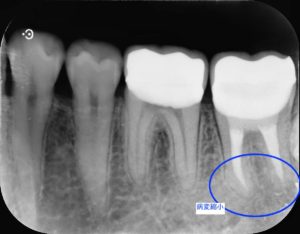

治療前

左下第二大臼歯部に不良補綴物をみとめたため、レントゲン検査を行うと根尖部透過像がみられた。根管内に破折器具がみられたため、破折器具の除去および根管内の感染除去を行った。経過観察後、根尖部透過像の縮小をみとめたため、歯冠修復を行った。